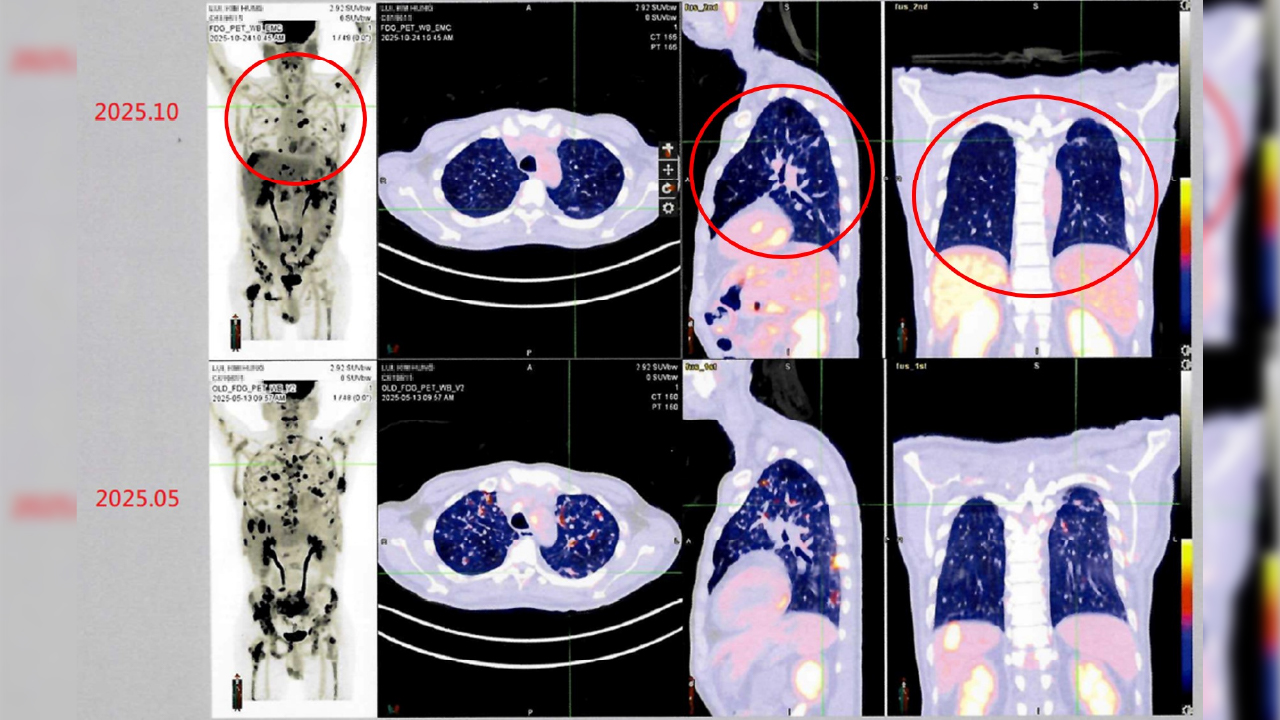

↑圖說:病人接受自體免疫細胞治療(DC-CIK)後,從治療前後影像資料對比(紅圈處),可發現癌細胞減少許多,顯示病情穩定。(圖片來源:衛生福利部雙和醫院提供)

衛生福利部雙和醫院有位來自香港的男性病患(50歲)。他於2024年在香港被診斷出罹患第四期肺癌,歷經多次傳統化療與標靶治療後,為尋求新的治療機會,他評估後決定來台灣進行自體免疫細胞治療(DC-CIK)。經過半年整合療程後,最新影像檢查顯示病情穩定,疼痛症狀明顯獲得緩解,體能與生活品質大幅提升。

莊主任指出:「對於部分晚期癌症患者,DC-CIK治療雖非取代性療法,但能與傳統治療(如化療、標靶或放療)相輔相成,有助提升免疫功能與整體生活品質。我們觀察到,許多接受治療的患者在臨床上都有生活品質改善與病情穩定的情況,顯示免疫細胞療法的潛力與價值。」